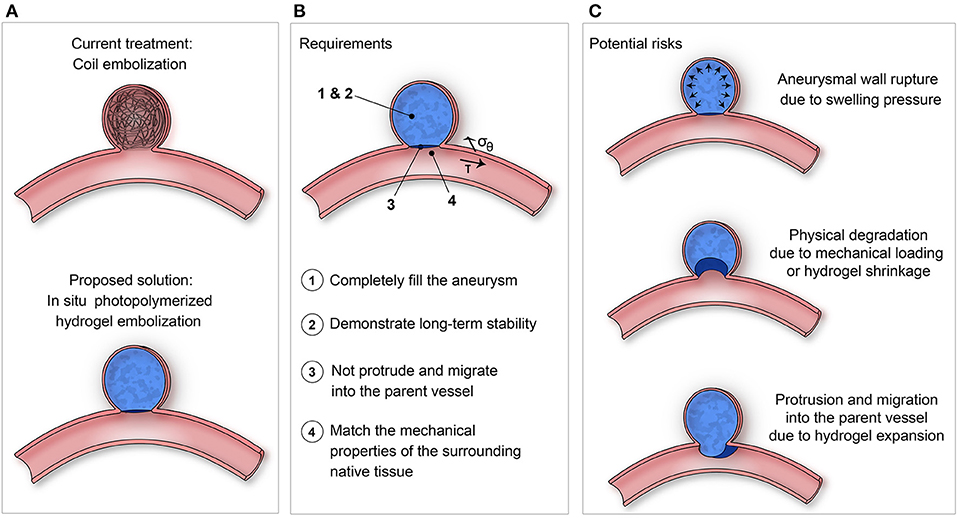

Poupart O., Conti R., Schmocker A., Pancaldi L., Moser C., Nuss K. M., Sakar M. S., Dobrocky T., Grützmacher H., Mosimann P. J., and Pioletti D. P., Pulsatile Flow-Induced Fatigue-Resistant Photopolymerizable Hydrogels for the Treatment of Intracranial Aneurysms, Front. Bioeng. Biotechnol., Vol. 8, January 2021. |

Poupart O., Schmocker A., Conti R., Moser C., Nuss K. M., Grützmacher H., Mosimann P. J., and Pioletti1 D. P., In vitro Implementation of Photopolymerizable Hydrogels as a Potential Treatment of Intracranial Aneurysms, Front. Bioeng. Biotechnol., April 2020. |